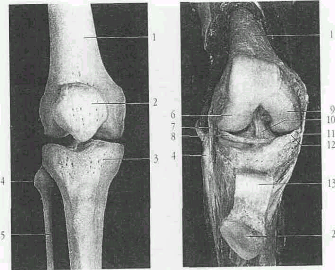

Рис.2 Костные элементы коленного сустава. Правый коленный сустав.

1 - бедренная кость;

2 - надколенник;

3 - большеберцовая кость;

4 - головка малоберцовой кости;

5 - малоберцовая кость;

6 - боковой (латеральный) мыщелок.;

7 - наружная боковая связка коленного сустава;

8 - латеральный мениск (межсуставной хрящ коленного сустава);

Реклама

9 - медиальный мыщелок коленного сустава;

10 - передняя крестовидная связка;

11 - внутренняя боковая связка коленного сустава;

12 - внутренний мениск (промежуточный диск коленного сустава;

13 - связка надколенника.

Рис 4. Правый коленный сустав вид сзади

13 - связка надколенника;

14. - задняя крестообразная связка.